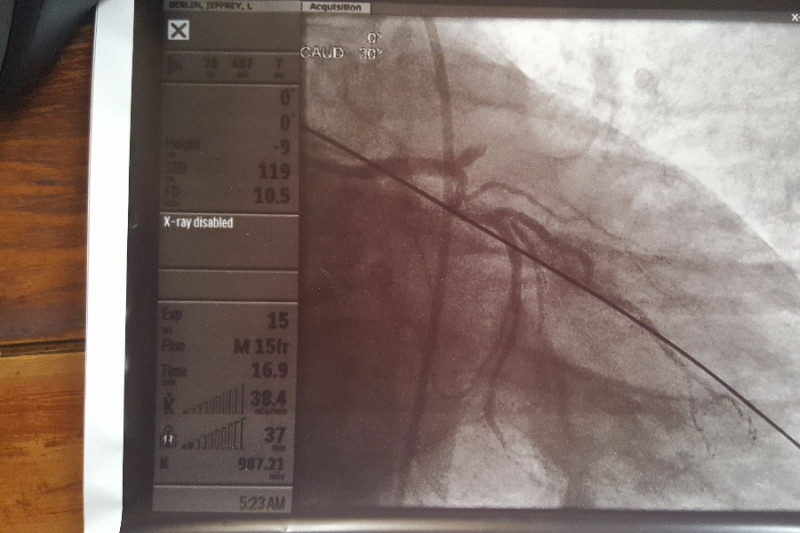

My wife and I were cycling on a flat trail on Sunday, August 13th, and I was having a bit of chest pain all during the ride. I blew it off as indigestion since I just passed a stress test last month. Late Monday evening, the pain got so bad I broke down and let my wife take me to the ER. I was having a heart attack. Turns out it was the "Widowmaker" artery that was 100% blocked.

After 2 stents and 48 hr with an aortic balloon, I'm stabilized. The hopsital experience is the least of my worries. The medication that I will have to be on for the rest of my life is going to be the problem. It is expensive and most of the cost is not covered under our insurance.